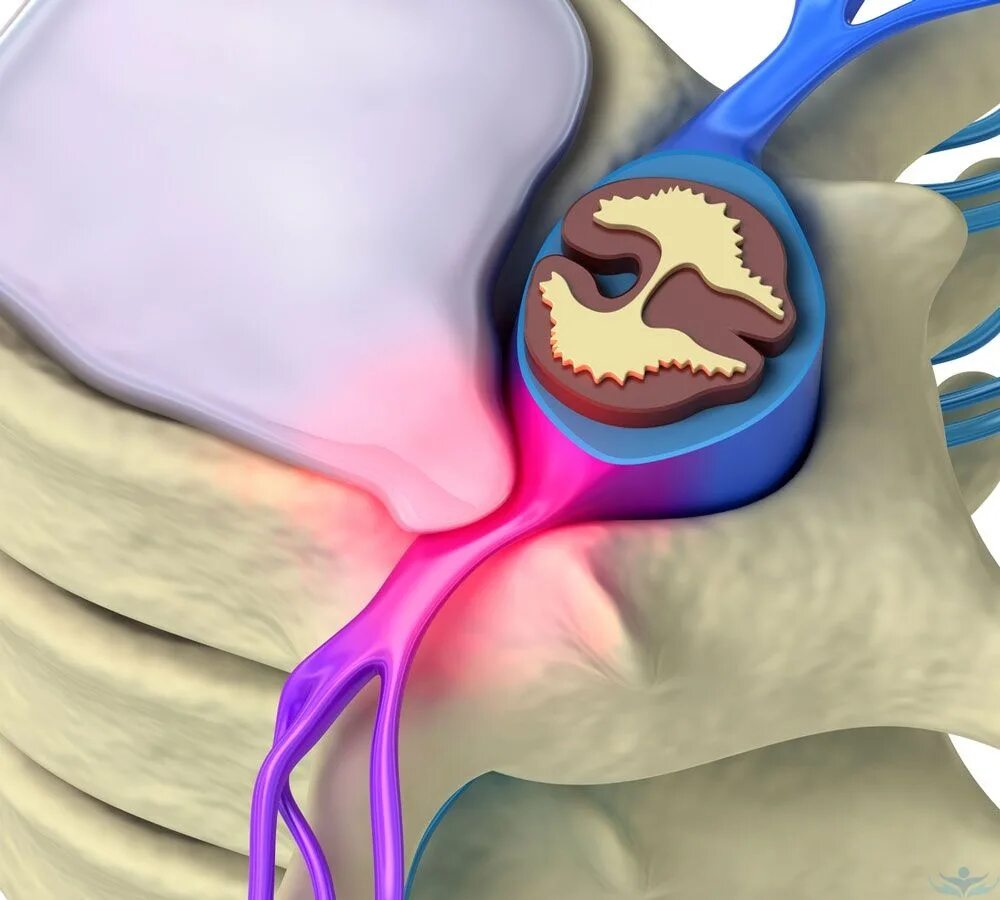

Диффузные кольца